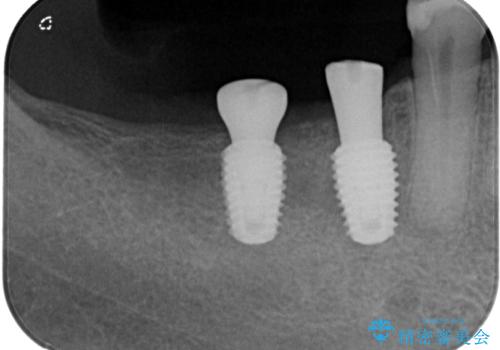

レントゲンで確認すると骨は十分にあるので通法通りインプラントによる補綴治療を行いました。